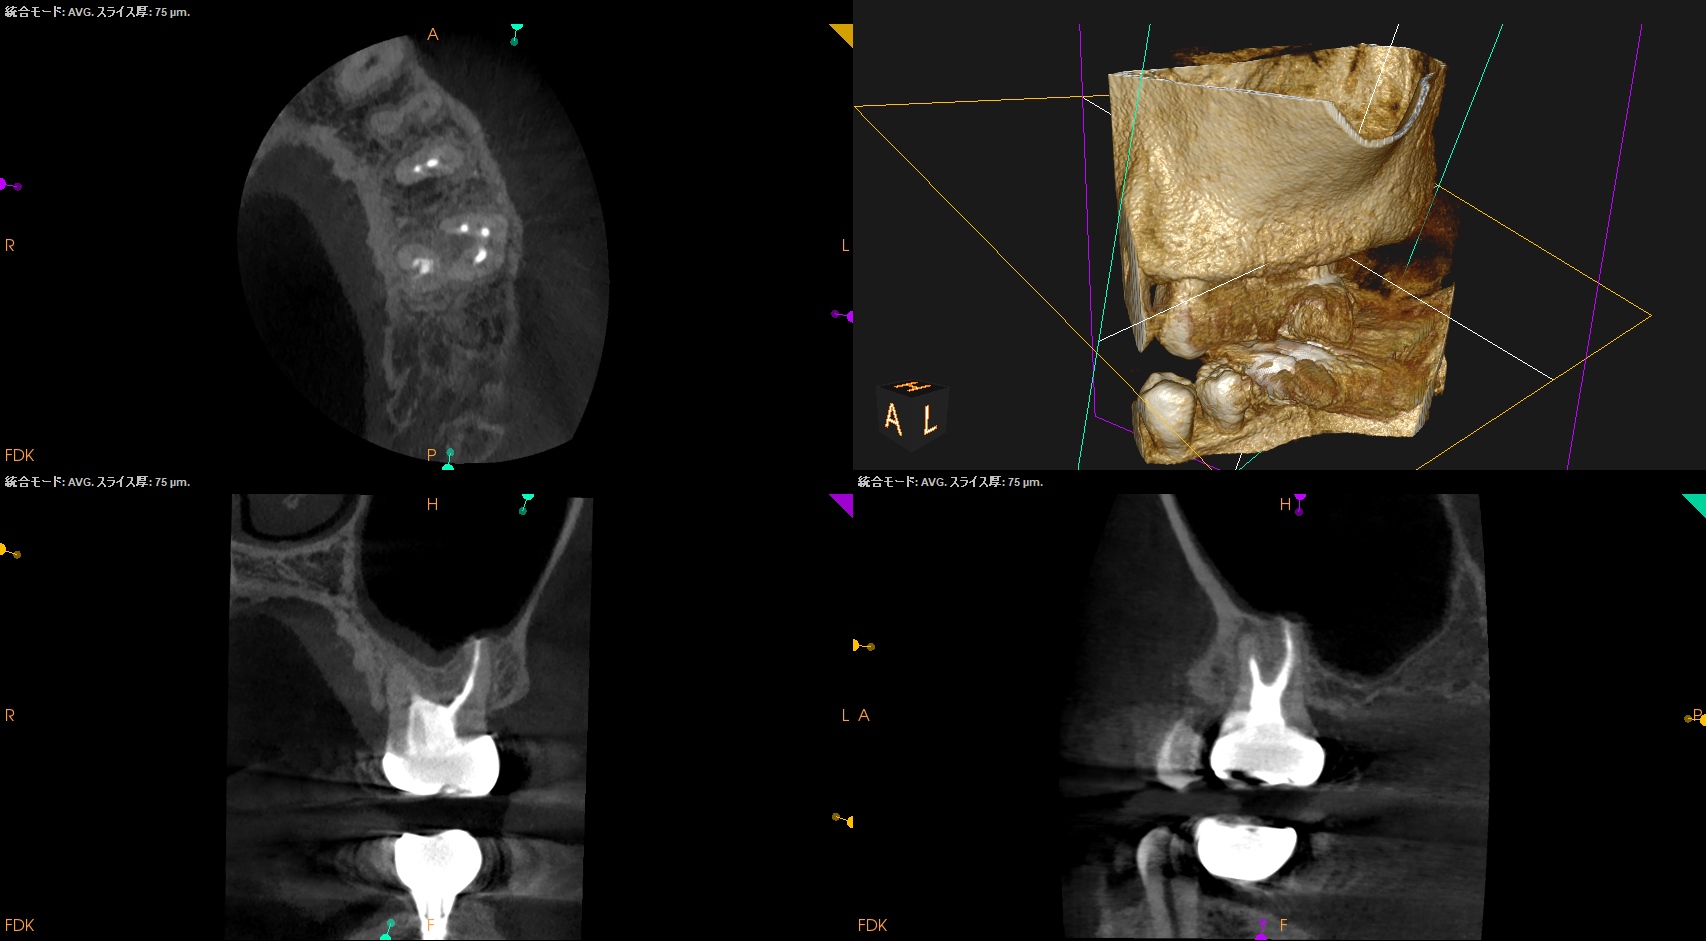

#13,14 RCT 2yr Recall(2025.4.8)

#13に咬合痛がある。

#13の根尖部に病変が見える。

#13

主根管に設定したB根管の根尖部の遠心側に根尖病変がある。

なんと…

96%の成功に入らなかったのだ。